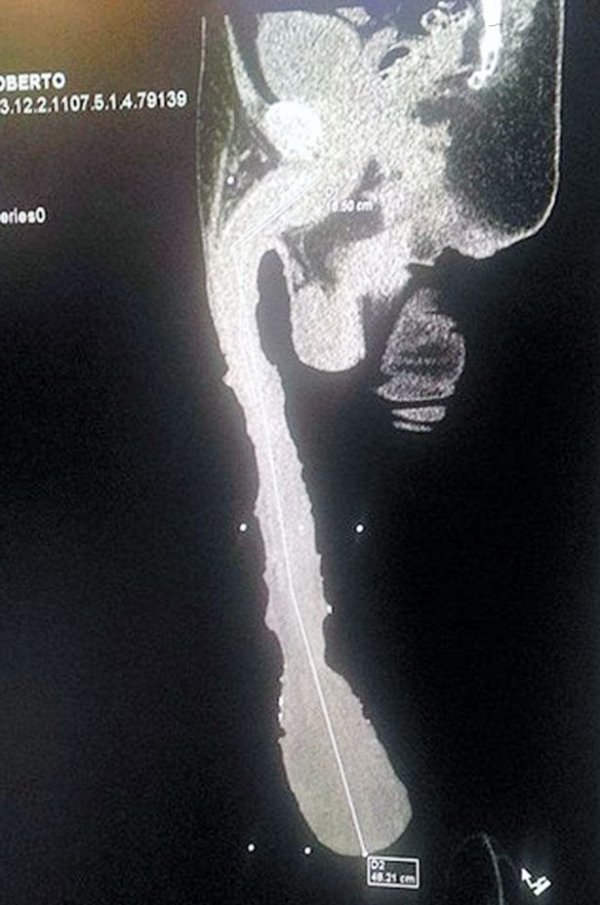

Tvrdi da je obdaren spolovilom dugim 48,2 cm, za što nudi i rendgensku snimku kao dokaz, ali kako ga citira The Sun, kaže da mu je impozantna alatka uništila život.

'Pa pogledajte koliki je, visi sve do ispod koljena. Ništa ne mogu raditi, nesposoban sam za bilo što i zato tražim da mi država da status invalida i pomogne mi. A nakon toga želim da mi u Guinnessu priznaju moj rekord', rekao je Cabrera i dodao da nema partnericu jer se žene plaše seksa s njim.